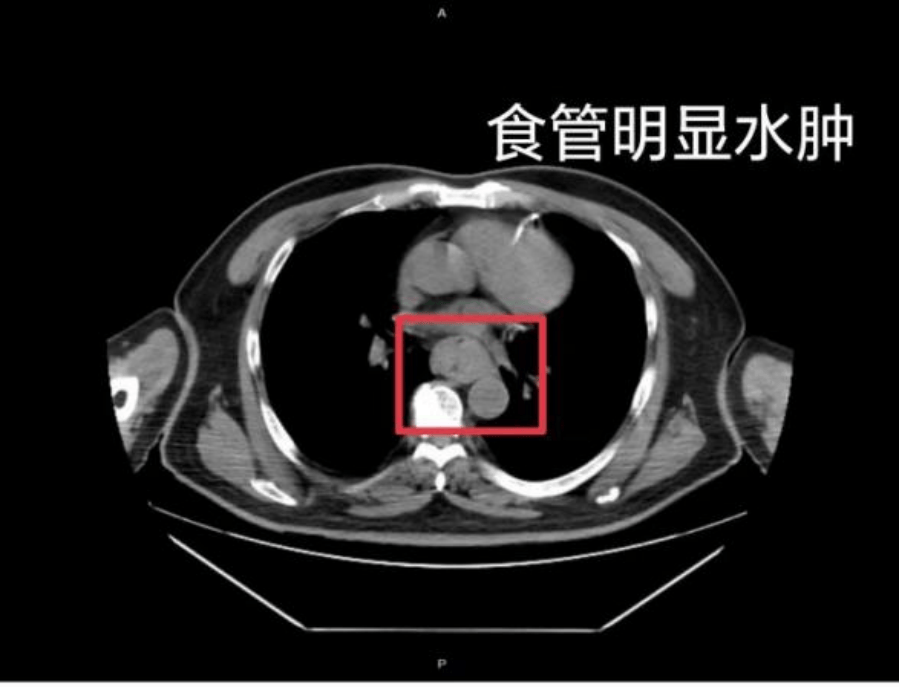

这样的情况并非个例,同样在近日,福州一位网友分享了自己因吃了一碗很烫的福鼎肉片导致呕血,并查出食管水肿的经历石蜡基原油。

据网友回忆,“自己去厕所尝试呕吐时,直接呕出了血,一大口鲜血从嘴里喷出,总共吐了两次石蜡基原油。”CT 结果显示,他的食管全部出现水肿损伤。